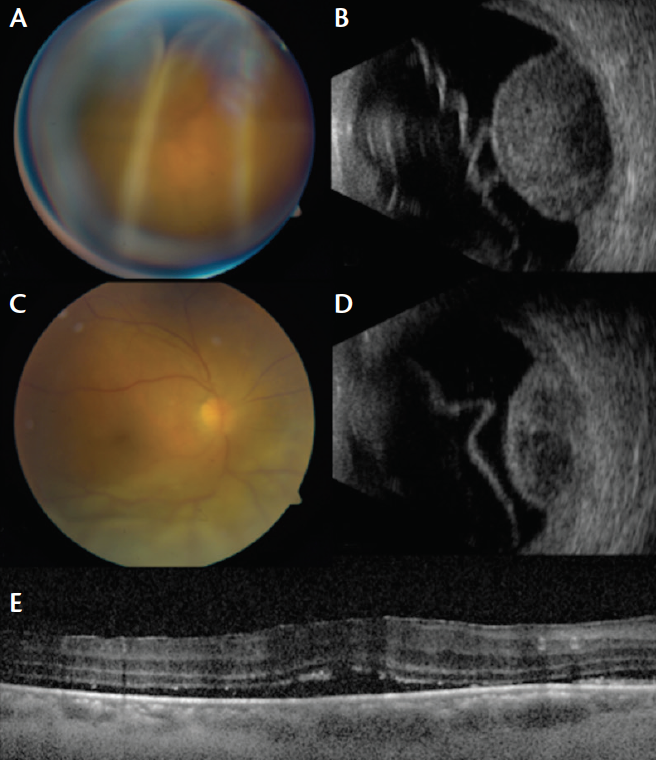

On ocular examination, best corrected visual acuity was light perception OD and 20/40 in his left eye (OS). Intraocular pressure was 19 mm Hg OD and 33 mm Hg OS. Anterior segment evaluation revealed pseudophakia in each eye (OU). Fundus examination OD (Figure, A) disclosed two yellow choroidal tumors associated with extensive exudative retinal detachment involving the macular region. The largest mass, located inferiorly, measured 19.0 mm in base and 10.4 mm in thickness, and the smaller tumor, located superiorly, measured 10.0 mm in base and 3.3 mm in thickness. Fundus examination OS showed a single yellow choroidal mass located superotemporally and measuring 9.0 mm in base and 1.9 mm in thickness. There was no retinal detachment OS. B-scan ultrasonography confirmed two solid, dome-shaped, choroidal masses with overlying subretinal fluid OD (Figure, B) and a smaller choroidal mass OS. Optical coherence tomography (OCT) through the lesions yielded poor quality images due to extensive subretinal fluid OD and peripheral location OS.

Figure. Fundus image of a 68-year-old black man with choroidal metastasis secondary to prostate carcinoma revealed a large choroidal mass with underlying extensive exudative retinal detachment and shallow subretinal fluid in the macular region (A). B-scan ultrasonography demonstrated a solid choroidal mass measuring 10.4 mm in thickness with overlying subretinal fluid (B). After 6 weeks of EBRT, the large choroidal mass shrank (C) to 6.4 mm in thickness (D), and near-complete resolution of subretinal fluid was confirmed on OCT (E).

These features were consistent with multifocal bilateral choroidal metastasis in a patient with systemic metastases from prostate carcinoma. Oncology systemic evaluation confirmed no sign of primary lung cancer. The patient was treated with 10 sessions of external beam radiotherapy (EBRT) to each eye. Six weeks after treatment, visual acuity improved to hand motion OD and 20/20 OS. The inferior choroidal mass OD showed regression (Figure, C) from 10.4 mm down to 6.4 mm in thickness (Figure, D), and the superior mass regressed from 3.3 mm to 1.6 mm, with dramatic reduction in subretinal fluid confirmed on OCT (Figure, E). There was complete regression of the tumor OS to a flat mass. This eye was managed conservatively with observation. Serial injection of periocular triamcinolone was planned to further reduce the subretinal fluid OD.